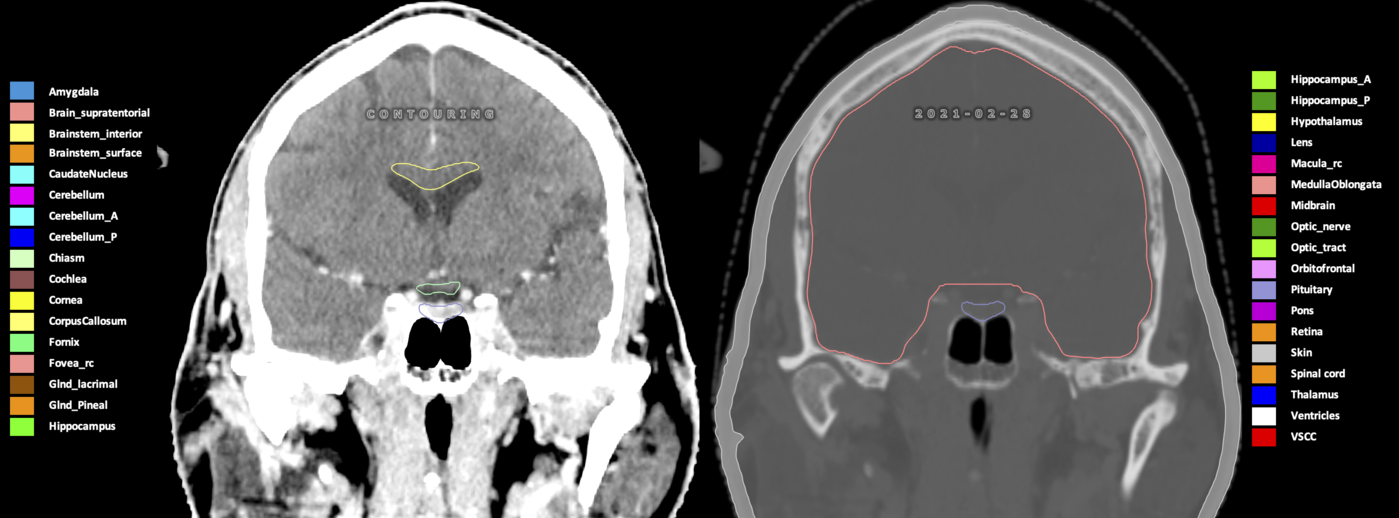

Eekers et al. have published an international neurological atlas for contouring of organs at risk in consensus with the European Particle Therapy Network (EPTN) in 2018 and an update in 2021. The purpose of this consensus atlas is to decrease inter- and intra-observer variability in delineating OARs relevant for neuro-oncology.

Included are all OARs known to be relevant for radiation-induced toxicity in neuro-oncology: brain, brainstem (midbrain, pons, medulla oblongata), chiasm, cerebellum (anterior & posterior), cochlea, cornea, hippocampus (anterior & posterior), hypothalamus, lens, lacrimal gland, optic nerve, pituitary, skin, and vestibular & semicircular canals. To further facilitate research on cognition, vision and radiological changes after irradiation of the brain, potential clinically-relevant OARs are included: amygdala, caudate nucleus, cerebellum (anterior & posterior), corpus callosum, fornix, macula, optic tract, orbitofrontal cortex, periventricular space (PVS), pineal gland, and thalamus.

Three-dimensional delineation of the 25 consensus OARs for neuro-oncology are shown on CT (WW/WL 120/40, 3000/600), 3T MR images, (T1Gd, T2FLAIR 1mm) and 7T MR (MP2RAGE 0.7 mm). All are presented in transversal, sagittal and coronal view.